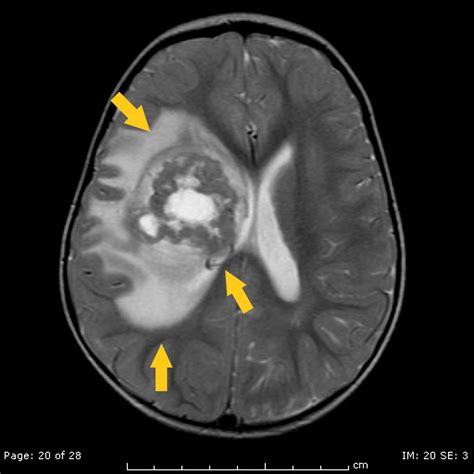

Diagnosis typically begins with advanced neuroimaging, such as MRI scans with and without contrast, to visualize the tumor's size and location. However, imaging alone is rarely sufficient. A definitive diagnosis is achieved through a surgical biopsy or total resection, followed by a rigorous pathological examination. Pathologists look for the loss of INI1 protein expression in the tumor cells, which serves as a molecular hallmark for an Atypical Teratoid Tumor.

• Atypical Teratoid Rhabdoid Tumor MRI